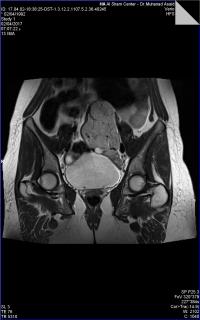

Medical imaging is an important investigative tool will help doctors to reach for the diagnosis of certain diseases, and the the advanced and high-quality imaging technologies are an important factor in maintaining the health of patients and accurate diagnosis of pathological lesions.